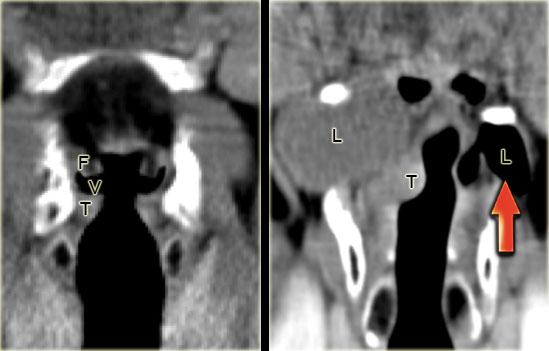

TRÁI: Hình CT mặt phẳng vành qua thanh quản với giải phẫu bình thường: dây thanh giả (F), dây thanh thật (T) và buồng thanh quản ở giữa (V). PHẢI: Túi thoát vị thanh quản thứ phát trong và ngoài chứa dịch do khối u nhỏ ngấm thuốc ở buồng thanh quản (T) gây tắc nghẽn buồng thanh quản. Bên trái là túi thoát vị thanh quản nguyên phát trong và ngoài chứa khí.

Cơ chế hình thành túi thoát vị thanh quản

Buồng thanh quản (v) là khe hở dạng khe giữa dây thanh giả và dây thanh thật (hình ngoài cùng bên trái).

Đây là mốc giải phẫu phân chia vùng trên thanh môn và thanh môn.

Buồng thanh quản kéo dài sang bên và sau đó lên trên vào khoang cạnh thanh môn.

Khi lỗ mở của buồng thanh quản bị khối u tắc nghẽn hoàn toàn, niêm mạc trong khoang cạnh thanh môn tiếp tục tiết dịch.

Điều này dẫn đến túi thoát vị thanh quản bên trong chứa dịch.

Cuối cùng, khoang cạnh thanh môn bị lấp đầy và túi thoát vị thanh quản bên trong sẽ trở thành bên ngoài bằng cách lan ra ngoài thanh quản qua màng giáp móng.

Khi lỗ mở của buồng thanh quản bị tắc nghẽn một phần, cơ chế van áp lực có thể tạo ra túi thoát vị thanh quản bên trong chứa khí, và cuối cùng có thể trở thành bên ngoài (hình bên phải, mũi tên đỏ).